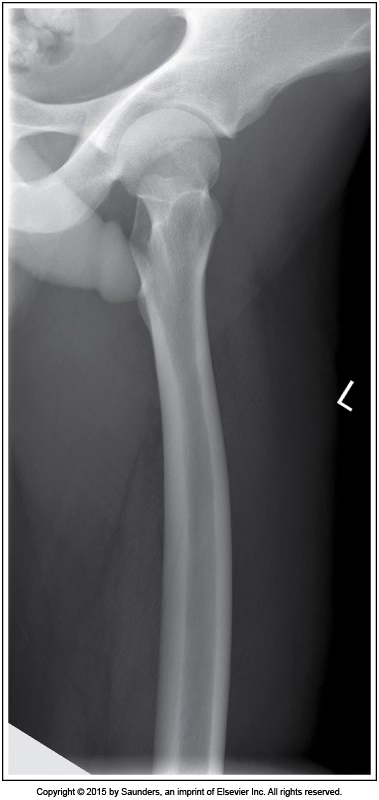

lateral femur

accurate positioning